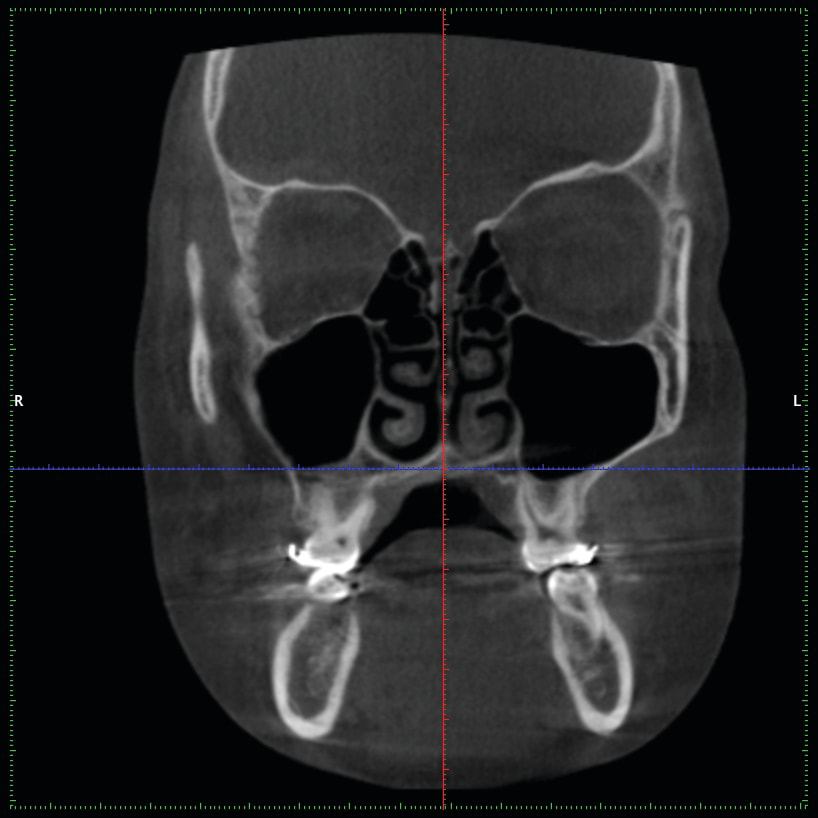

4. Any patient that will have a temporary skeletal anchorage device placed. Most clinicians that have become proficient and confident with the placement and use of TSADs place them on approximately 23% of the case treatment planned in their practices. When evaluating the placement site in all three planes of space, the clinician can become very exact with locating structures that should be avoided. More TSADs are being placed in the infazygomatic area. A 3D image is the best way to locate the optimal area of placement for stability in this area. See Figure 13 and note the thickness of the bone in the infrazygomatic crest. Compare the thickness of the bone in Figure 14. The bone in this figure demonstrates bone that is too thin for placement of the TSADs. More TSADs are being placed in to palatal approach. TSADs placed in the premaxilla are an area of placement that is vitally important to visualize the anatomy in this area. One should consider the thickness of bone in this area to avoid the tips of the TSADS from penetrating the nasal cavity and to avoid the roots of the teeth in this area. See Figure 15 through Figure 17. When skillfully placed in adequate bone, the use of TSADS certainly allows orthodontist to treat their patients more consistently and predictably. The use of 3D imaging aids the clinician in the placement and use of the TSADs.